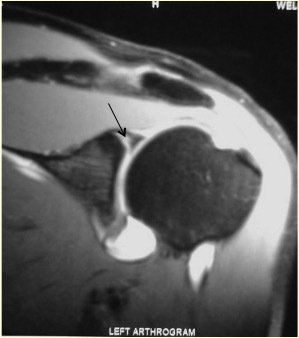

A labral tear is an injury to the labrum or “bumper” around the rim of the socket of the shoulder. A SLAP lesion is a tear of the labrum at the top of the socket.

Slap Mra

This is a condition that results in symptoms of pain, “popping” or “clunking” of the shoulder. Occasionally the arm may feel “dead”. Pain may often only be experienced with overhead activities. Examination may show signs of pain with certain movements of the shoulder and signs of subtle restriction of movements. Pain may be reproduced on specific provocative tests. X-rays are often normal. Special imaging with an MRI scan is often necessary to obtain further information about the state of the labrum and the ligaments. In some instances an MR arthrogram (MRI scan after injection of contrast fluid in the joint) may be requested.